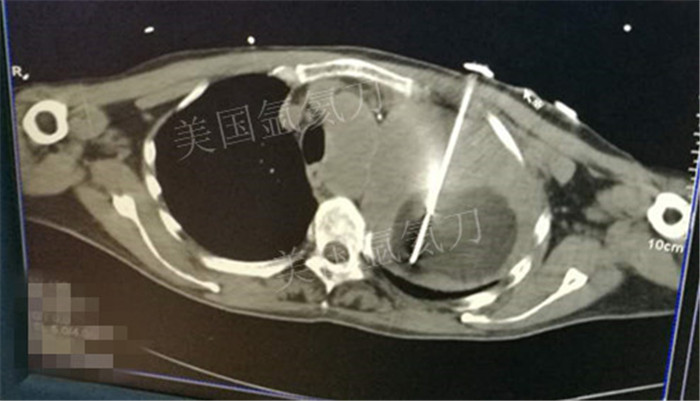

下一篇:氩氦冷冻治疗最大径8.2肿瘤,冰球最大径7.9